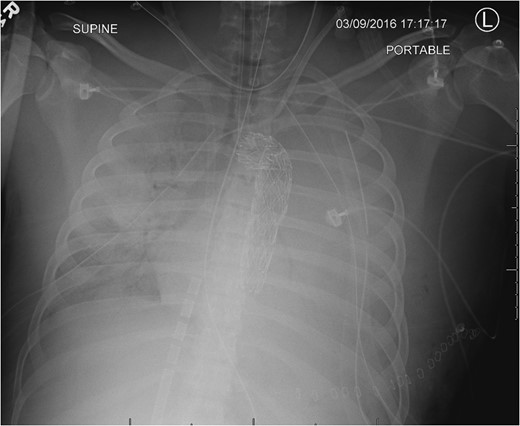

CXR following chest closure on postop day 3 demonstrated the aortic stent, multiple life support lines and bilateral lung opacification from the severe persistent respiratory failure.